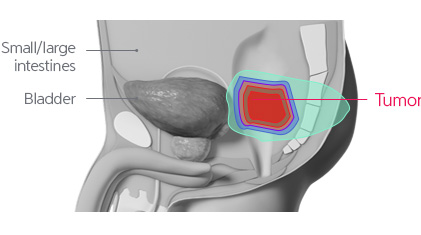

Due to functional and cosmetic reasons, surgical operations may be restrictive. Although high dose radiotherapy is implemented, the level of radiation transferred is limited. Therefore, it is difficult to implement high dose therapy with the X-ray treatments and side effects are common.

Proton cancer decreases concerns of side effects associated with radiotherapy retreatment and high dose radiation treatment while transferring a sufficient amount of radiation to obtain high tumor control rates.

For recurrent rectal cancer that has been previously treated with radiotherapy, it is known that tumor removal is difficult and that there are limitations in the cosmetic and functional aspects when treated with surgical operations. Therefore, there are many cases where high dose radiotherapy is implemented. In such cases, even if treated through intensity modulated radiotherapy, side effects from radiation exposure to the surrounding normal organs are common, and for 5 years, the tumor control rate has been less than 50%. However, proton treatment is expected to decrease the level of radiation exposed to the surrounding normal tissues while transferring a high dose of radiation to the tumor for effective removal.